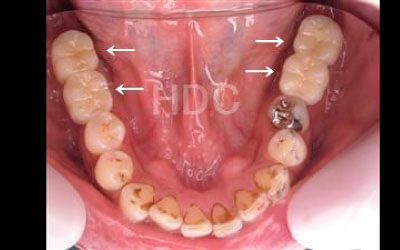

お口の状態や噛み合わせによって異なるため一概には言えませんが、一般的には奥歯、特に大臼歯と言われる一番奥とその隣の二番目の歯の部分がお勧めです。

この2本の奥歯は、噛み合わせの力の60%以上を支えているため、ここをインプラントでしっかり治療することが望ましいです。